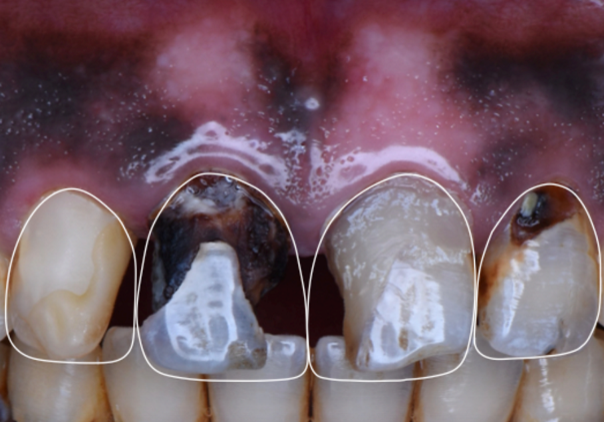

Treatment options 1: Crowns related to #11, 12, 21, Direct veneer #22 and class V composite restoration related to #13.

2: Build up related to #11, 12, 21, Direct veneer #22 and class V composite restoration related to #13.

Treatment options were discussed with the patient and the patient chose the second option.

Step 1 – Digital smile design Digital smile designing done according to golden proportions for a predictable clinical outcome.